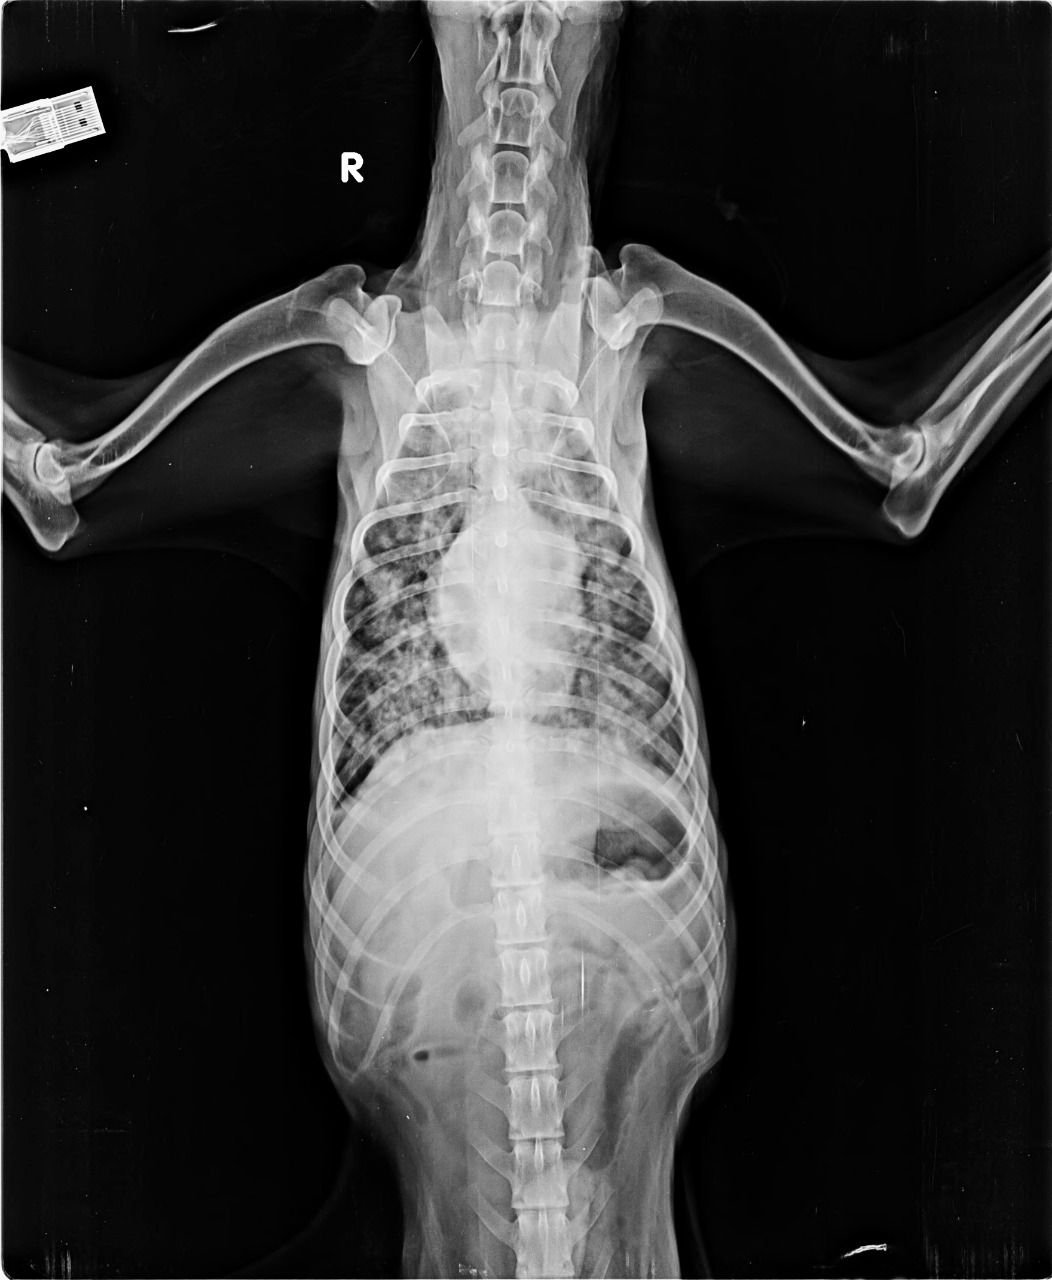

With a aim of “सर्वे भवन्तु सुखिनःI सर्वे सन्तु निरामया:I”, X RAY HOUSE, ANAND started Animal Imaging department for small animals.

We are pioneer of radio-diagnosis in small animals like dog, cat, rabbit, turtle etc. in Gujarat.

NOTE: Given the sensitivity to motion, all animals for MRI study are anesthetized and monitored during the procedure.